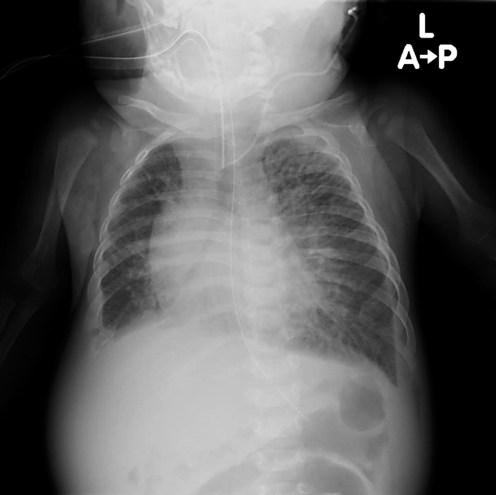

肥大型心筋症を合併した心房中隔欠損症に対して開窓付閉鎖術が奏功した1例Fenestrated Closure of an Atrial Septal Defect for Left Ventricular Diastolic Dysfunction in an Early Infant with Hypertrophic Cardiomyopathy